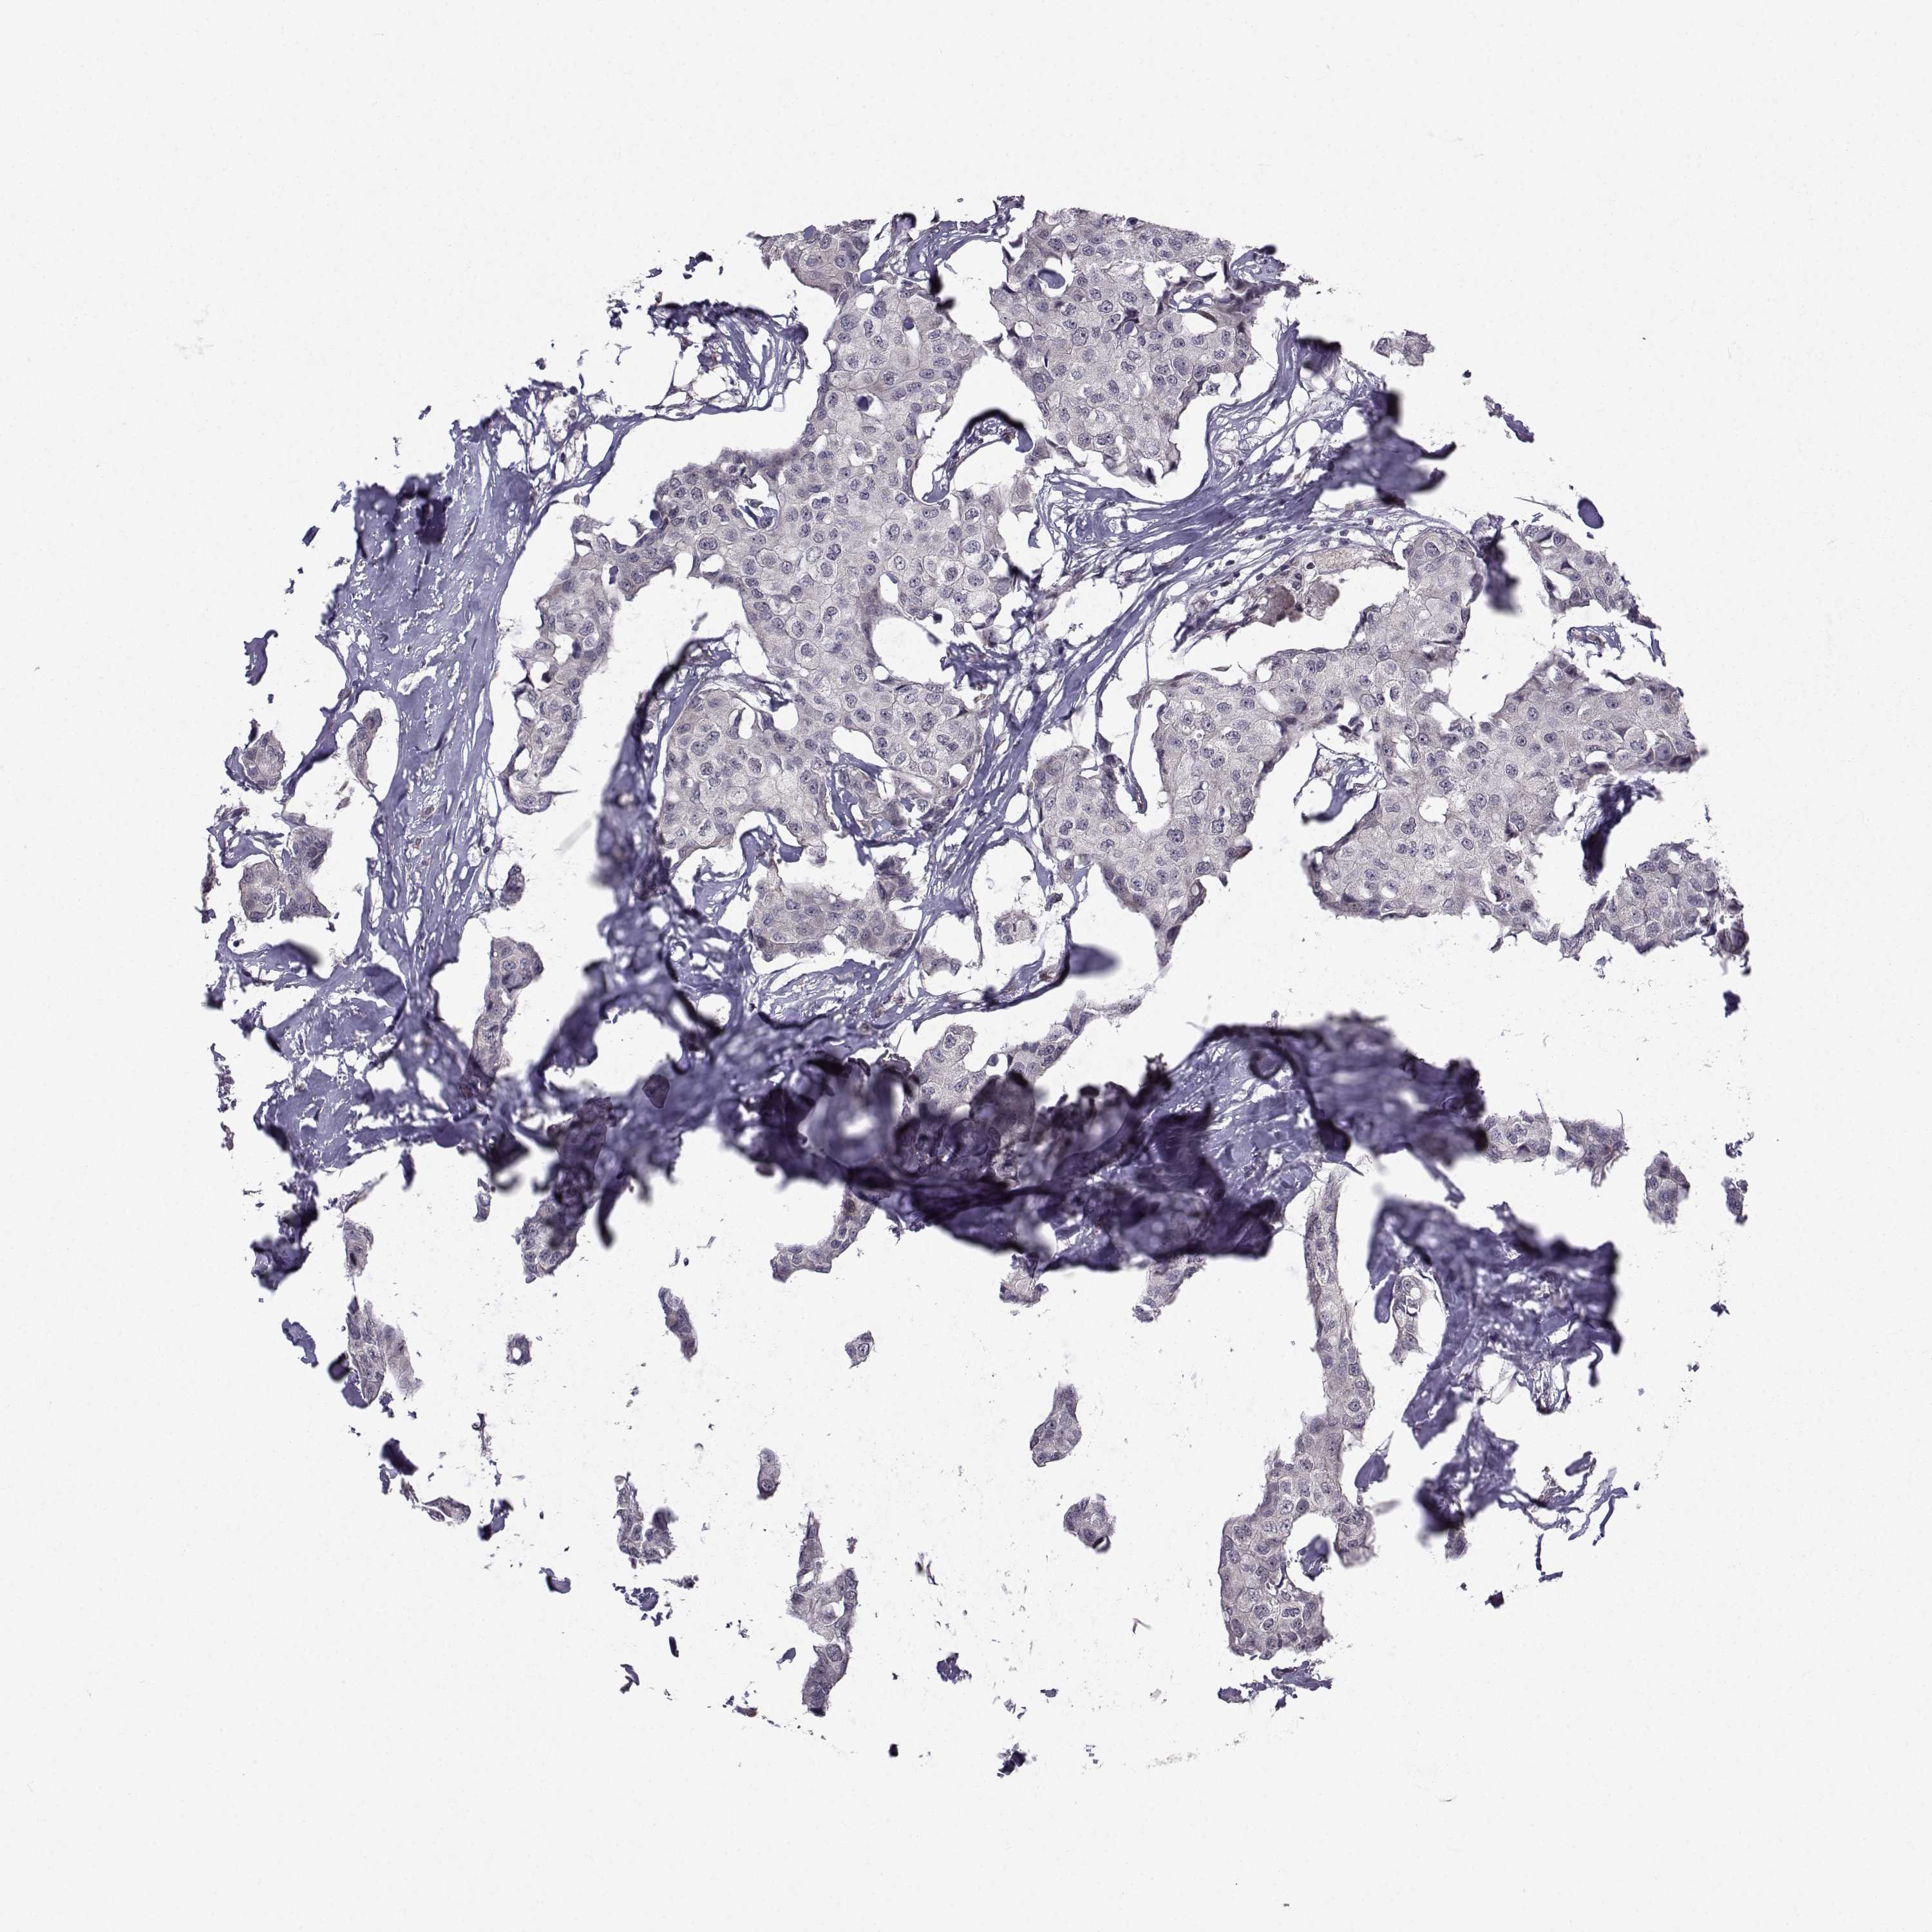

BRCA TCGA BRCA VALIDATION PROTEIN EXPRESSION

ANTIBODIES

AND

VALIDATION